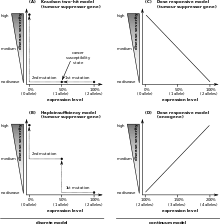

Unlike oncogenes, tumor suppressor genes generally follow the "two-hit hypothesis," which implies that both alleles that code for a particular protein must be affected before an effect is manifested. This is because if only one allele for the gene is damaged, the second can still produce the correct protein. In other words, mutant tumor suppressors' alleles are usually recessive whereas mutant oncogene alleles are typically dominant.

There are exceptions to the "two-hit" rule for tumor suppressors, such as certain mutations in the p53 gene product. p53 mutations can function as a "dominant negative," meaning that a mutated p53 protein can prevent the function of normal protein from the un-mutated allele.[3]

Other tumor-suppressor genes that are exceptions to the "two-hit" rule are those that exhibit haploinsufficiency, including PTCH in medulloblastoma and NF1 in neurofibroma. An example of this is the p27Kip1 cell-cycle inhibitor, in which mutation of a single allele causes increased carcinogen susceptibility.[4]